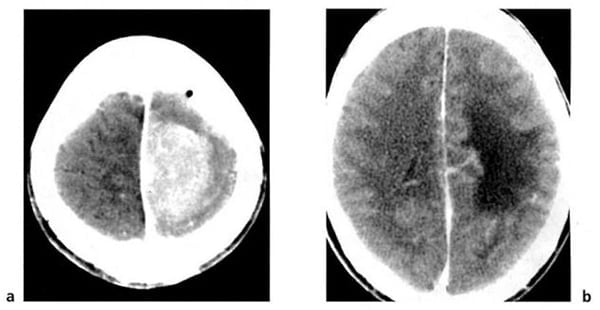

Hình 1.43. Khối máu tụ tươi trong não ở một trẻ nhỏ. Máu có mật độ cao trong bán cầu não bên phải, phù mật độ thấp bao quanh. Tụ dịch mãn dưới màng cứng hai bên. Đây là một trường hợp trẻ bị bạc đãi.

Hình 1.45. Máu tụ ngoài màng cứng. Khối tụ hình thấu kính hai mặt lồi ở vùng thái dương có mật độ cao tự nhiên, đẩy nhu mô não và xóa mờ não thất bên bên phải.